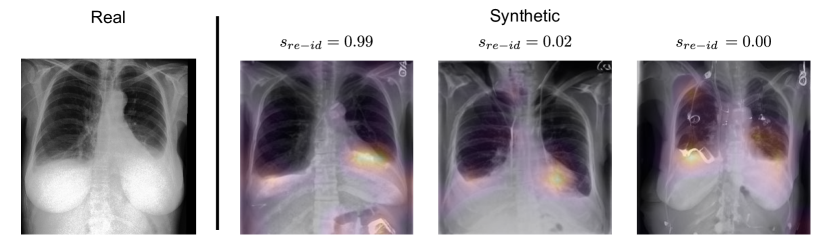

Visualising of How Synthetic Examples are Memorised.  We now focus on analysing Grad-CAM++ (Chattopadhay et al., 2018) heatmaps of the fθreidsuperscriptsubscript𝑓𝜃𝑟𝑒𝑖𝑑f_{\theta}^{re-id} network in Figure 5(a) and some samples of synthetic images and their associated conditioning information in Figure 5(b). For the explainability heatmap, we used the second-order gradients of the fourth layer of the ResNet-50 (which is a common choice for this architecture555https://github.com/jacobgil/pytorch-grad-cam#chosing-the-target-layer).

Refer to caption

(a) Grad-CAM++ heatmaps over the fθreidsuperscriptsubscript𝑓𝜃𝑟𝑒𝑖𝑑f_{\theta}^{re-id}. From left to right, the first synthetic image contains identifiable information about the real image in the areas towards the bottom of the lungs. The other two images do not contain identifiable information as defined by the re-identification score sreidsubscript𝑠𝑟𝑒𝑖𝑑s_{re-id}.

Figure 5: Illustration showing how synthetic images, obtained by using the same prompt of the real image as conditioning, relates to the real image as well as the prompt. We try to mitigate privacy risks in these illustrations because the license of MIMIC-CXR 777https://physionet.org/content/mimic-cxr/view-license/2.0.0/ does not allow sharing data. In 5(a), the “Real” image is actually a synthetic image that is very similar to the original image. In 5(b), we blurred the real images.